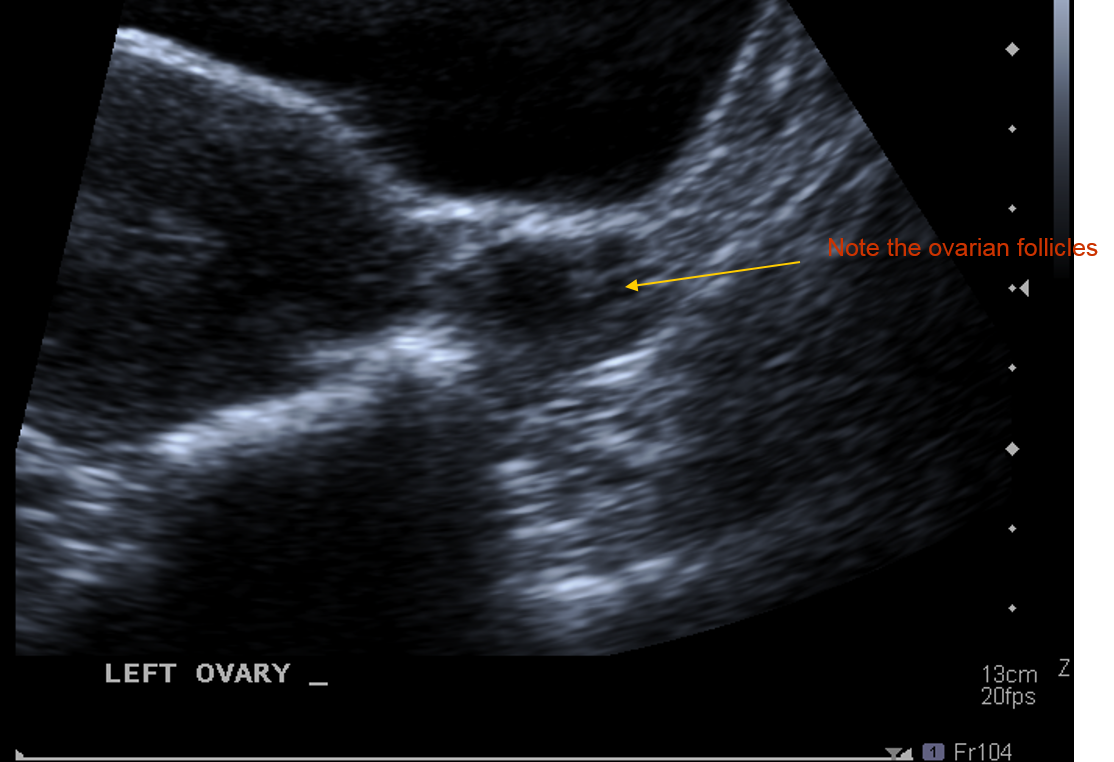

What vascular strcture can the ovaries be shown to be closely related to ?

The R and L external iliac vessels